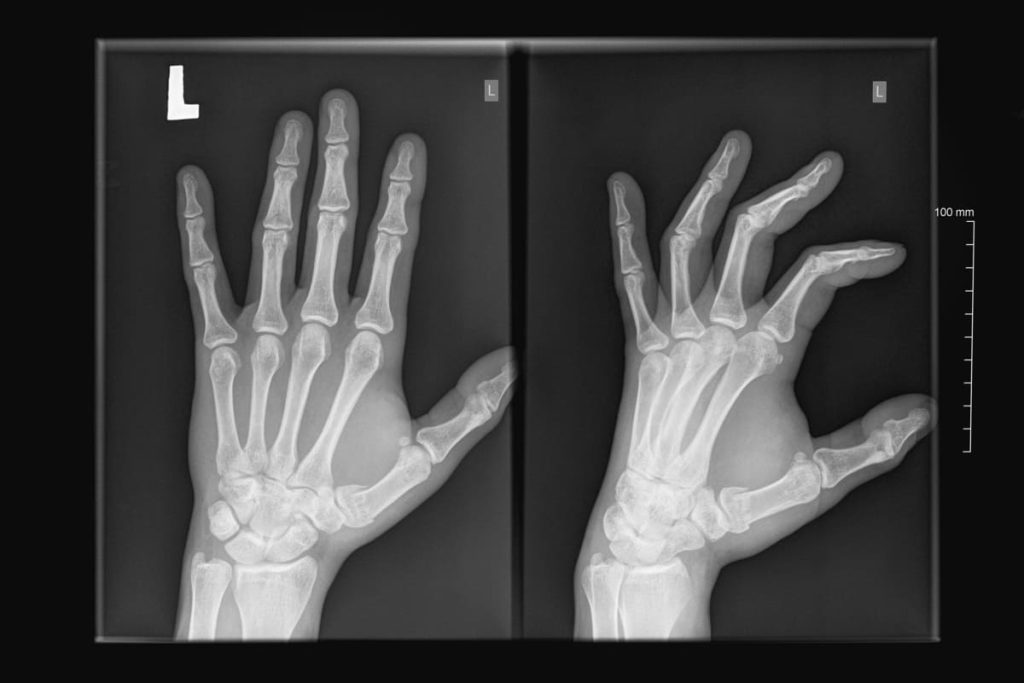

radiographie de la main 1

Dupuytren’s Disease: Rupture of the Flexor Digitorum Profundus Tendon

Study of rare complications of Dupuytren’s disease, including tendon rupture, and surgical options to restore finger mobility.

Deforming conditions: Such as Dupuytren’s disease, which leads to progressive finger contracture toward the palm. Surgical procedures can correct deformities and improve hand function.